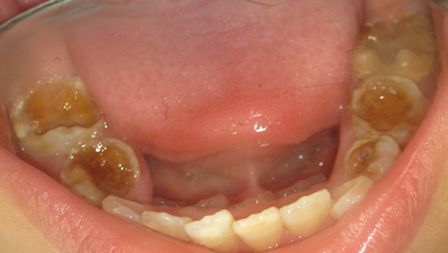

- MANEJO DE LA CARIES DE LA INFANCIA TEMPRANA

Esta es una de las problemáticas de salud pública que de manera desafortunada no tiene programas de atención de amplia cobertura por la complejidad de su manejo integral.

Los pacientes que son afectados por esta entidad siempre son de difícil manejo, tanto en lo comportamental como en la dificultad propia de la rehabilitación necesaria para cada caso especial.

MASIVAS DESTRUCCIONES DE LAS CORONAS DENTALES POR CARIES EN LA DENTICION TEMPORAL.

Esta entidad requiere siempre tratamiento direccionado y ejecutado por especialista en Odontología Pediátrica, cuya formación y experiencia permitan desarrollar los cambios en el contexto familiar y la eliminación de focos sépticos y rehabilitación correspondiente necesaria en estos pacientes.